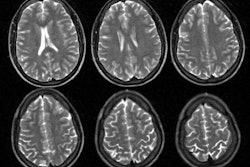

We evaluated ictal 99mtechnetium hexamethyl propylene-amine-oxime single-photon

emission computed tomography (SPECT) in 22 children with electroclinical

features of frontal lobe epilepsy (FLE). Ictal SPECT demonstrated unilateral

frontal hyperperfusion in 20 of 22 children (91%) (one lobar, two frontocentral,

six dorsolateral, six frontopolar, three orbitofrontal, one medial frontal, and

one insula), concordant with electroclinical lateralization in 19 of 20 (95%).

Hyperperfusion was evident in the ipsilateral basal ganglia in 16 of 22 (73%)

and the contralateral cerebellum in 14 of 22 children (64%). Interictal SPECT

showed unilateral, localized frontal hypoperfusion concordant with

electroclinical lateralization in only two of 22 children (9%). Ictal SPECT